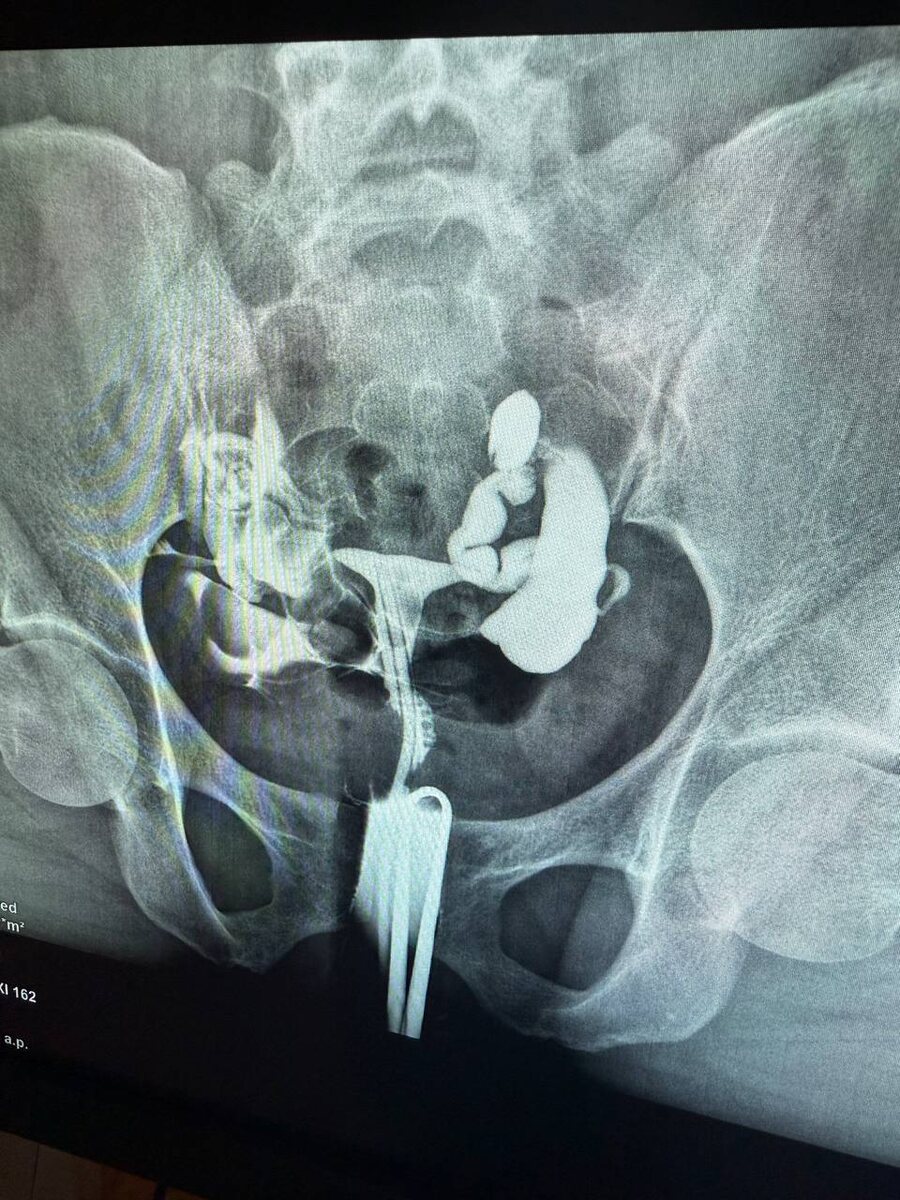

Пациентка 28 лет , в октябре была операция по поводу эндометрроидных кист ( рецидив после первой операции) и выраженный спаечный процесс

Операцию выполняла я , в конце был введен противоспаечный гель в брюшную полость . Сегодня данная пациентка пришла на оценку проходимости маточных труб . Честно - она сама не ожидала , что будут проходимы трубы , и я признаюсь тоже- так как спаечный процесс был тотальный - трубы , яичники , кишечники - всё в спайках ! Но какая была радость когда - справа абсолютно хорошо проходимая труба , слева- увы нет . Но тем не менее, даже с одной проходимой маточной трубой возможна самостоятельная беременность!!! 🤰 и я искренне верю и знаю , что детям быть 🙏🤍 Ваша доктор Замалтдинова РР🌹

Пациентка 28 лет , в октябре была операция по поводу эндометрроидных кист ( рецидив после первой операции) и выраженный спаечный процесс. Операцию выполняла я , в конце был введен противоспаечный гель в брюшную полость . Сегодня данная пациентка пришла на оценку проходимости маточных труб . Честно - она сама не ожидала , что будут проходимы трубы , и я признаюсь тоже- так как спаечный процесс был тотальный - трубы , яичники , кишечники - всё в спайках !

Но какая была радость когда - справа абсолютно хорошо проходимая труба , слева- увы нет . Но тем не менее, даже с одной проходимой маточной трубой возможна самостоятельная беременность!!! 🤰 и я искренне верю и знаю , что детям быть 🙏🤍